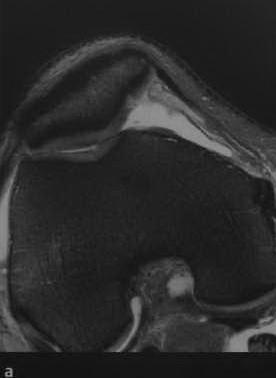

Патология и диагностика коленного сустава: что нужно знать